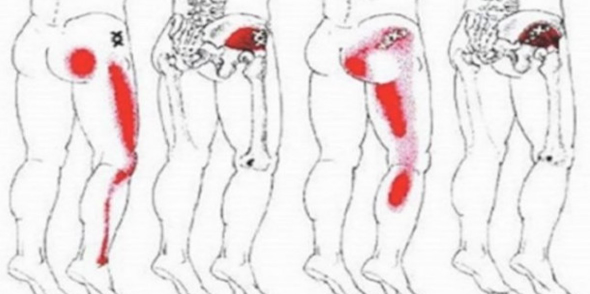

🩻 Simptomi išijasa

Ako niste sigurni da li vaš bol potiče od išijasa, obratite pažnju na ove simptome:

Bol koji počinje u donjem dijelu leđa ili kuku i širi se niz nogu.

Peckanje ili utrnulost u nozi.

Bol se pogoršava prilikom sjedenja.

Slabost ili poteškoće u pomjeranju noge ili stopala.

Iznenadni probadajući bol pri pokretu.

Konstantan bol u predjelu zadnjice.